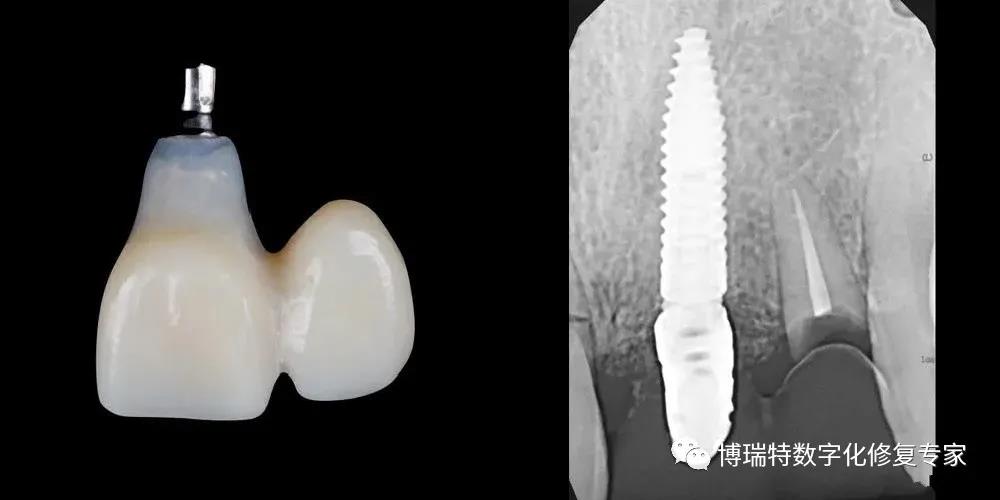

8226; 利用患者21天然牙冠制作种植体支持式螺丝固位临时修复体,21螺丝孔从腭侧穿出;

8226; 试戴临时修复体,调整邻接,调181015;至正中、前伸和侧方181015;均无接触。临时基台加力至15N;

8226; 术后根尖片显示临时基台就位良好;

8226; 术后CBCT 。